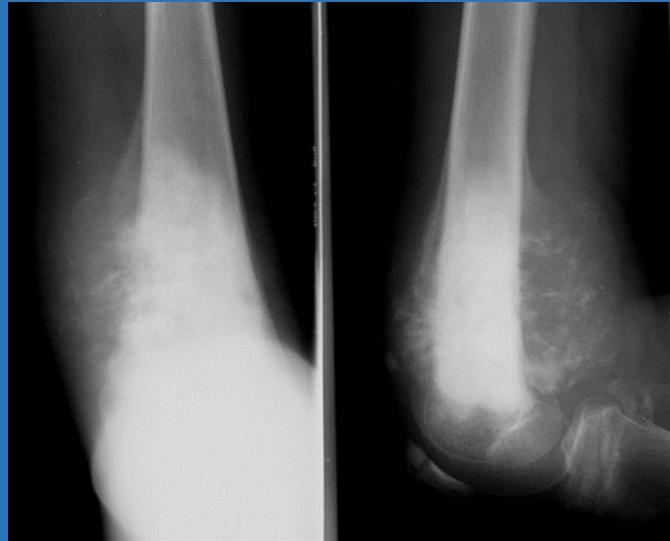

| Compartment Syndrome | Increased pressure within a closed fascial compartment, leading to reduced tissue perfusion, hypoxia, and irreversible muscle and nerve damage. Causes: Fractures (especially tibia/forearm), severe soft tissue trauma, arterial injury, burns, tight casts/dressings, post-ischemic reperfusion swelling, IV fluid extravasation, and bleeding disorders (e.g., hemophilia). High-Risk Notes: Pain may be absent in altered consciousness, children (monitor analgesia response), polytrauma, sedated/epidural cases, or concomitant nerve damage. Open fractures do not always decompress pressure. Gross/Clinical: -tense, shiny leg swelling with blisters in compartment syndrome.Imaging: - Intraoperative fasciotomy | History/Symptoms: Pain out of proportion to the injury (e.g., a “bursting” sensation), which is not relieved by analgesia. Clinical Features (The 5 P’s): - Pain with passive stretch (early, key sign; e.g., ankle dorsiflexion for leg, wrist for forearm). - Paresthesia (early). - Palpable tense swelling (shiny skin, blisters: clear=mild, serosanguinous=severe, bloody=worst; dusky/pallor skin). - Pallor, Paralysis, Pulselessness (late, ominous signs; pulses often palpable until late). Investigations: Primarily a clinical diagnosis (high suspicion key). Compartment pressure measurement can confirm: absolute pressure >30 mmHg or Delta Pressure (Diastolic BP - Compartment P) ≤ 25 mmHg. | Initial: ABCs, supplemental oxygen. Remove all circumferential dressings, casts (bivalve to skin), and splints. Elevate the limb to heart level (not above; higher reduces inflow). Correct any hypotension. Surgical: Urgent Fasciotomy if no response within 1h or confirmed pressure (prophylactic in high-risk like major osteotomy). Release all compartments/skin with long incisions; debride necrotic muscle via 4C’s (early: pink/red, soft, contracts/bleeds on pinch; late: dark, firm, no response); preserve neurovascular. Wound open (bulky dressing/splint, VAC, or boot-lace gradual closure); repeated inspections x48h; coverage in 3-5 days (skin graft usual; flap if nerves/vessels/bone exposed). | Cellulitis, Deep Vein Thrombosis (DVT), Arterial occlusion, Severe soft tissue injury without compartment syndrome; equivocal cases in polytrauma. | Complications: Volkmann’s ischemic contracture (permanent deformity, weakness, sensory loss, chronic pain). Contraindications (Fasciotomy): Confirmed >48h (irreversible damage, high infection risk from dead tissue); crush injuries with already necrotic muscle. |